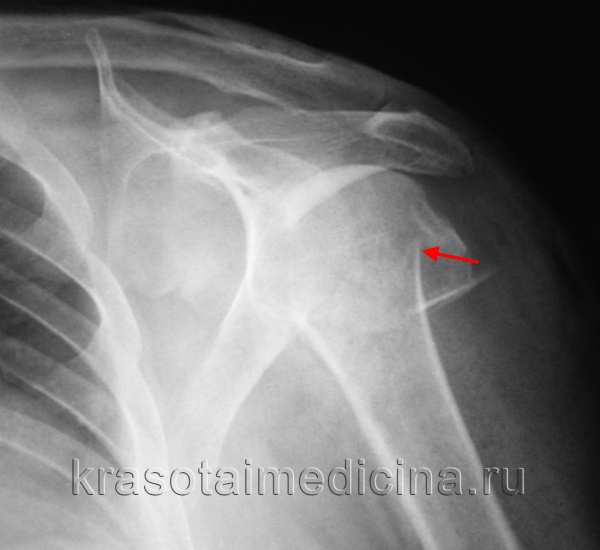

КТ плечевого сустава. Оскольчатый перелом хирургической шейки плечевой кости со смещением отломков. Дистальный отломок (красная стрелка) вколочен в проксимальный отломок (синяя стрелка).